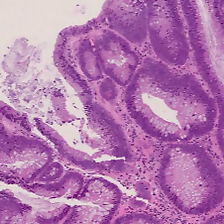

Fig. 1: Example of 800×\times800µm patches for the six UniToPatho colorectal polyps classes.

UniToPatho is a dataset of annotated high-resolution H&E-stained images, comprising different histological samples of colorectal polyps, collected from patients undergoing cancer screening. The dataset is a collection of the most relevant patch images extracted from 292292292 whole-slide images (simply slides in the following), in accordance with UniTo pathologists’ evaluation. The slides are acquired through a Hamamatsu Nanozoomer S210 scanner at 202020×\times magnification (0.4415 µmtimes0.4415micrometer0.4415\text{\,}\mathrm{\SIUnitSymbolMicro m}/px), as exemplified in Fig. 1. Each slide belongs to a different patient and is annotated by expert UniTo pathologists, according to six classes as follows: